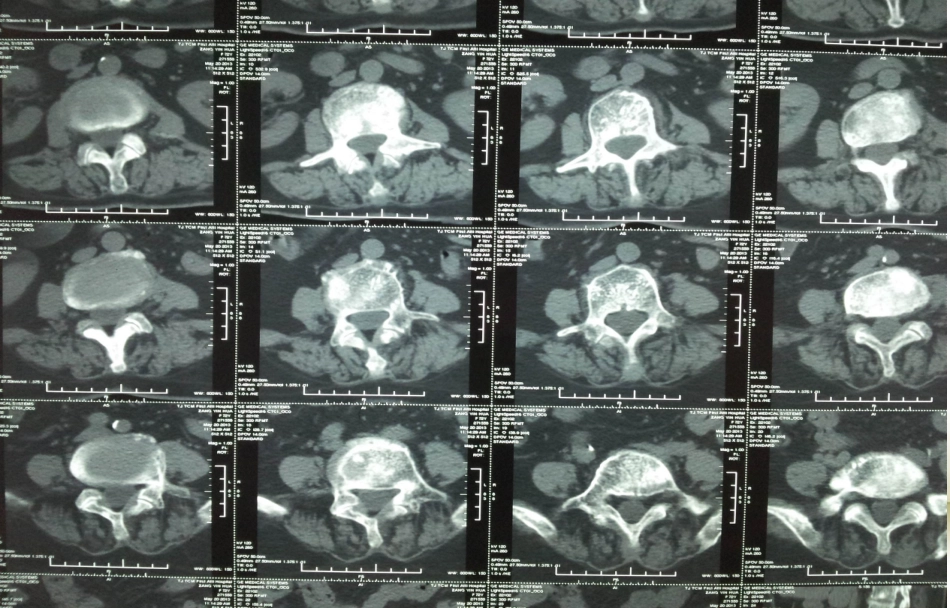

骨转移瘤藏某,女,72岁,腰腿痛CEA1440.76FER724.4519片段5.46CA199464.010CA12574.30什么是成骨型转移?什么是溶骨型转移?各自有何特点?破骨、成骨骨组织的细胞成分包括骨原细胞、成骨细胞骨细胞和破骨细胞。正常成人骨组织保持着一种平衡的、受控制的骨重组过程,首先破骨细胞吸收其周围骨组织然后再由成骨细胞在同一位点形成新骨。细胞学角度破骨……骨质破坏成骨……骨质增生二者都是转移性骨肿瘤的分型。转移性骨肿瘤:1.通常是多发性的。2.多见于躯干骨,尤其是脊柱,长骨通常以膝、肘以上好发。3.最好发于红骨髓区或松质骨内。4.按病变的密度和形态分为溶骨型、成骨型、混合型(和囊状扩张型)。注:骨髓是存在于长骨(如肱骨、股骨)的骨髓腔,扁平骨(如胸骨、肋骨)和不规则骨(髂骨、脊椎骨等)的松质骨间网眼中的一种海绵状的组织,能产生血细胞的骨髓略呈红色,称为红骨髓。成年人的骨髓分两种:红骨髓和黄骨髓。红骨髓能制造红细胞、血小板和各种白细胞。溶骨型1.最多见2.表现:骨松质中多发或单发小的虫蚀状骨破坏区边缘不规则,无硬化边,病变发展,破坏融合扩大,形成大片溶骨性骨质破坏区,骨皮质也被破坏,但一般无骨膜增生。3.可形成局限软组织肿块,常并发病理性骨折。脊椎广泛受侵,常易并发病理性压缩骨折,椎旁多可见局限性对称性软组织肿块。4.椎间隙正常。椎弓根多受侵蚀、破坏。溶骨型成骨型1.少见2.见于前列腺癌、乳腺癌、肺癌、膀胱癌等的转移。3.表现为松质骨中斑片状或结节状高密度影密度均匀一致,常多发,境界清除或模糊。骨皮质多完整。骨外形大多不变。4.常发生在腰椎与骨盆。混合型兼有溶骨型和成骨型的骨质改变。囊状扩张型很少见。转移灶呈囊状膨胀性骨破坏。边界清楚,皮质膨出,可薄厚不均。特别提示:转移性骨肿瘤常为多发,单发转移性骨肿瘤少见诊断有一定困难,尤其是发生于长骨的溶骨性转移性骨肿瘤,需与原发的骨肿瘤相鉴别:单发转移性骨肿瘤易发生病理性骨折,病史短、发展快,多无骨膜反应,很少出现软组织肿块。注:骨膜是骨表面除关节外所被覆的坚固的结缔组织包膜。骨膜反应,又称骨膜增生,指在病理情况下骨膜内层的成骨细胞活动增加所产生的骨膜新生骨。组织学上可以见到骨膜内层成骨细胞增多,形成新生骨小梁。X线表现:显示为骨皮质外面局限性或广泛性的层状、带状、放射状、花边状、毛刷状或三角形高密度影。哪些肿瘤易发生何种类型的骨转移?骨转移是肿瘤发展过程中的最常见并发症,晚期前列腺癌或乳腺癌病人中,大约70%伴有骨转移,其它癌症,例如肺癌,肠癌,胃癌子宫癌,直肠癌,甲状腺癌或肾癌中,15~30%病理学角度:转移瘤多为腺瘤,肉瘤仅占少数一般不能确定原发肿瘤的部位,仅有少数分化较好的转移瘤有助于原发肿瘤的定位。前列腺癌、膀胱癌、鼻咽癌可表现为成骨性转移。乳腺癌在部分骨骼表现为成骨性转移,在另一部分骨表现为溶骨性转移。肿瘤骨转移的发生机制1.血液循环学说2.“种子土壤学说”血液循环学说“种子土壤学说”正常成人骨组织不断地进行着“重新塑造”在这个过程中,骨释放出大量的生长因子,从而为肿瘤细胞的着陆与繁殖提供了良好的环境1889年,斯蒂芬*佩吉特首先提出了肿瘤转移的"种子-土壤"学说,这一学说可以很好地解释为什么骨组织是多种肿瘤细胞偏爱的转移位点并得到了骨转移动物模型研究的支持如何诊断骨转移瘤?临床表现:疼痛;病理性骨折(破骨)骨转移癌引起疼痛的机理:1.肿瘤转移至骨组织,引起破骨细胞活性增加导致骨质溶解即骨破坏;2.同时肿瘤细胞能分泌一些致痛介质如前列腺素乳酸等加重疼痛。实验室指标:1.肿瘤标志物高2.骨质破坏……血钙高3.酸性磷酸酶ACP(前列腺癌)、碱性磷酸酶ALP升高ALP来源于不同组织,受到各个组织器官疾病影响较大特异性较差,骨性碱性磷酸酶(B-ALP)较ALP能更好地反映成骨细胞活性,多发性骨转移瘤患者B-ALP大多数都明显升高,并随着病情的进展进行性的升高。影像学检查病理活检如何诊断骨转移瘤CT,MRI,ECT(SPECT,PET)ECT(EmissionComputedTomography),即发射单光子计算机断层扫描仪,是一种利用放射性核素的检查方法。ECT成像的基本原理:放射性药物引入人...